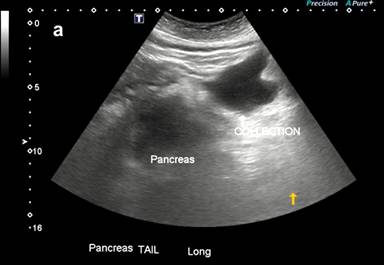

An ultrasound was performed in the emergency which revealed a thickened pancreas and 140 mL of peripancreatic fluid collection at the pancreatic tail. There was fatty infiltration of liver but no gallbladder involvement (Figure 1a). Antibody testing for autoimmune pancreatic insulin insufficiency did not show any abnormalities except a low C-peptide (Table 3). HbA1C was 13.1%. The septic screen performed at initial presentation was normal.

Figure 1. a. Initial ultrasound finding demonstrating edematous pancreas and adjacent fluid collection. b. Follow-up ultrasound demonstrating hypoechoic region consistent with pseudocyst. |

He was commenced on a normal diet day 3 of his admission. Repeat ultrasound showed resolution of pancreatic inflammation and a well-defined hypoechoic region adjacent to the pancreatic tail consistent with a pseduocyst (Figure 1b). He had an additional hypoechoic region in the body of the pancreas suggestive of residual edema.